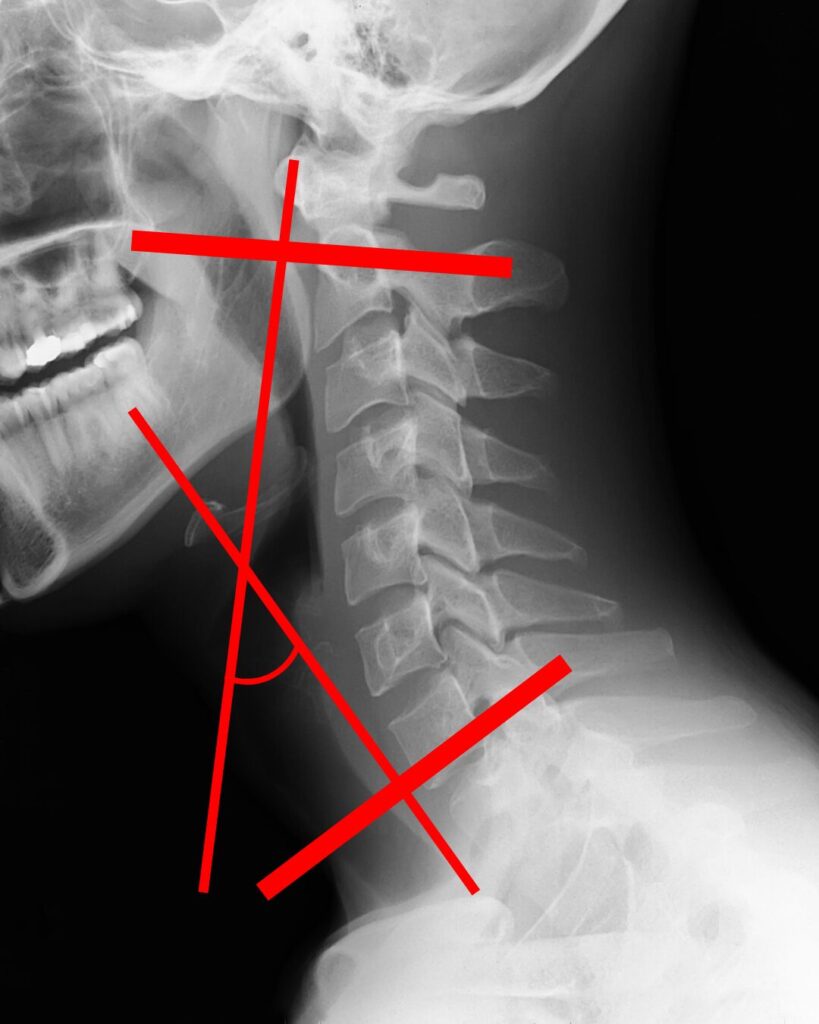

ストレートネックの基準

基本的には「触診」もしくは

正しく判断するには

画像所見でないと判断できないとされています!

第2頸椎の上端と第7頸椎の下端がなす角度が

30 °以下だと

ストレートネックと言われます!